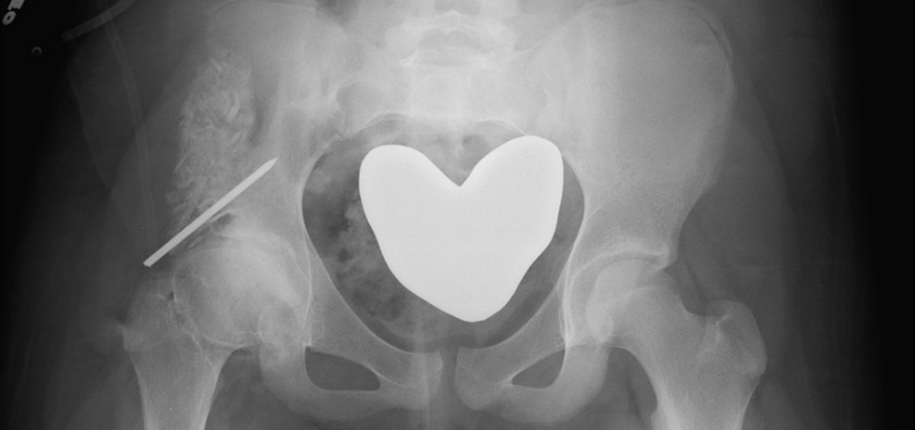

In this video tutorial, Keith explains why we have stopped using gonadal shielding on some of our x-ray exams.

[ot-video][/ot-video]